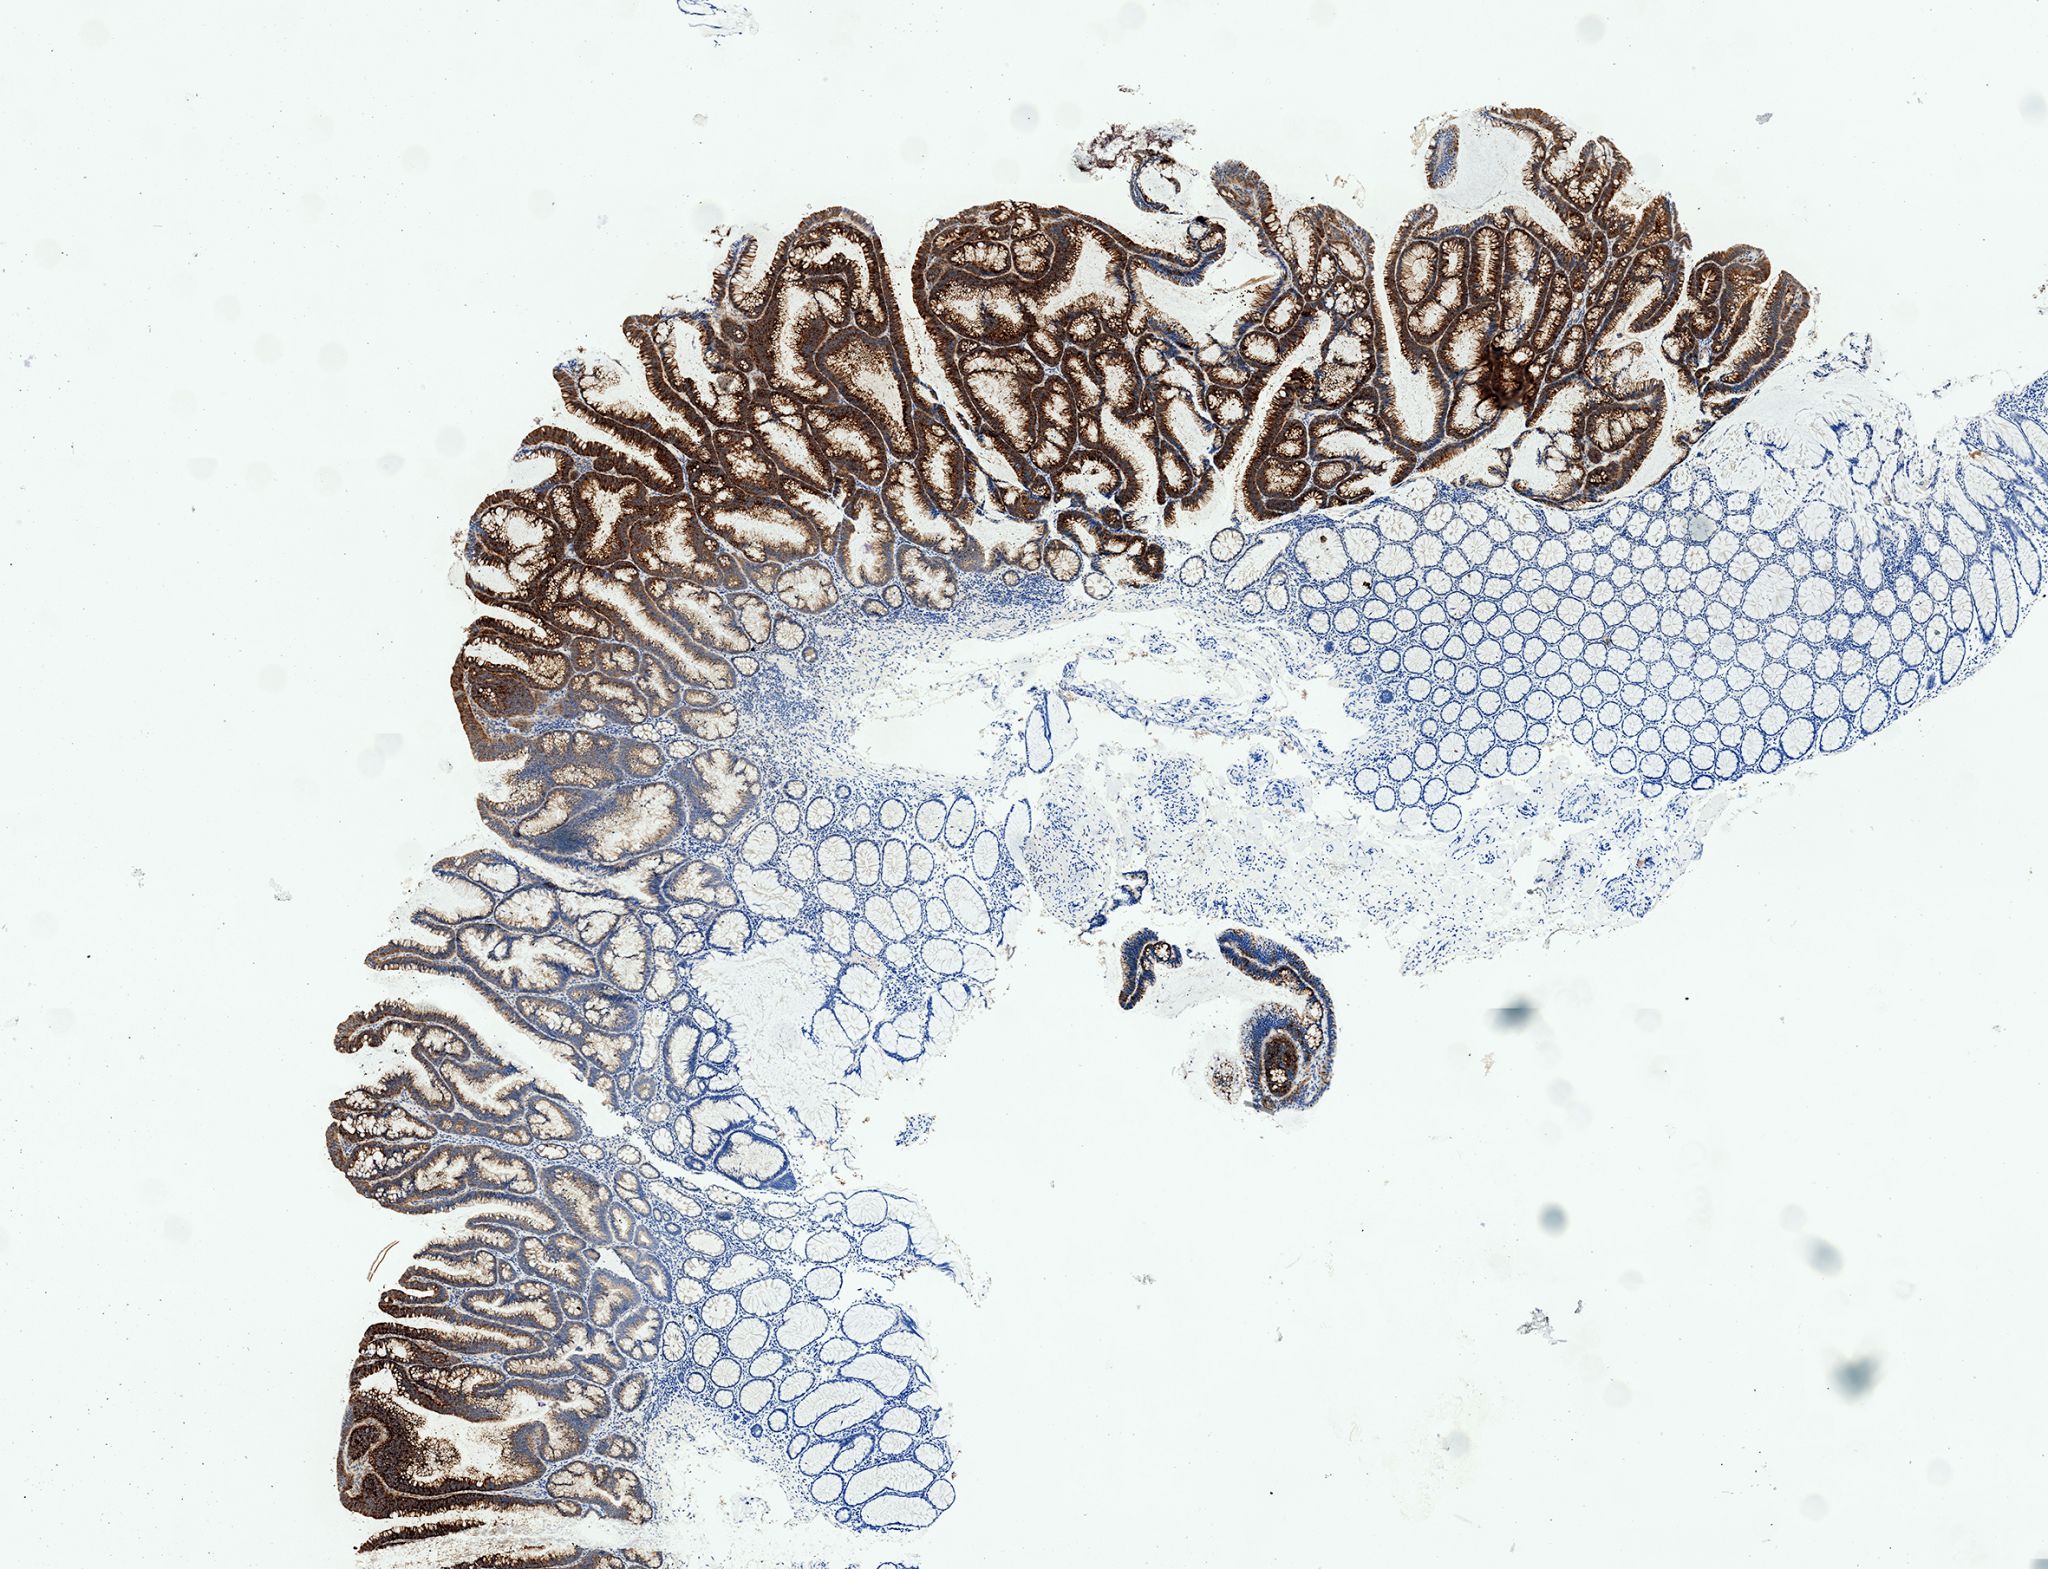

Das Bild zeigt einen entarteten menschlichen Darmpolypen mit immunohistochemischer Anfärbung des Biomarkers DIA2 zur Erkennung früher Darmkrebsstadien (Adenoma) und das angrenzende gesunde Gewebe. (© Henner Farin/GSH)

In der vorliegenden Studie entdeckten er und seine Kollegen erstmals eine tumorspezifische  molekulare Reaktionskette, die durch Wnt ausgelöst wird. Dafür nutzten die Forscher dreidimensionale Darmkulturen, die sie aus gesundem menschlichem Darmgewebe heranzüchteten, sogenannte „Organoide“. Organoide sind eine neues Verfahren der Biomedizin. Im Labor werden Darmzellen als Zellverband vervielfältigt, so dass sie organähnliche Eigenschaften erhalten und zum Beispiel die Wirkungsweise von Medikamenten im Darm untersucht werden kann. Mit Hilfe dieser Mini-Därme konnten die Forscher die Wnt-Aktivität in Darmtumoren und den Stammzellen eines gesunden Darms vergleichen. Dazu schalteten sie das Tumor-Suppressor Protein APC gezielt aus, wodurch Krebsvorläuferstadien (Adenome) entstanden. Interessanterweise wurde dabei eine ganz andere Palette an Genen durch Wnt aktiviert, als dies in den gesunden Zellen der Fall war.